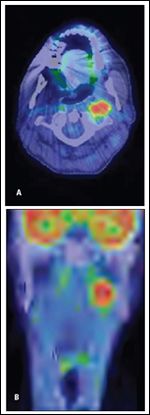

FIGURE 1

PET/CT Images of the Second Relapse in a Patient With a Stage IVA HPV-Positive Squamous Cell Carcinoma of the Head and Neck

DR. BOWLES: Dr. Ree, can you comment on the PET/CT scan at the time of the patient’s second relapse?

DR. ALEXANDER REE: There is asymmetric soft tissue fullness and metabolic activity at the skull base in the lateral retropharyngeal space that obliterates portions of the left longus capitis, the medial pterygoid muscle, and the posterior belly of the digastric muscle (Figure 1). There is abnormal fullness of the submandibular space, the hypopharynx, and the inferior aspect of the left nasopharynx, which results in asymmetric effacement of the overlying left fossa of Rosenmller. There is no evidence of cortical disruption of the mandible or hyoid bone, or of erosions of the thyroid cartilage. Both the soft tissue fullness and abnormal PET activity extend into the region of the left tonsillar surgical bed.

DR. BOWLES: Sadly, we met our patient when he had a second local recurrence, which occurred less than one year after he concluded his first therapy. His disease manifested as a PET-avid lesion in the left retropharyngeal/parapharyngeal region and was deemed unresectable (Figure 1). What can be done at this point?